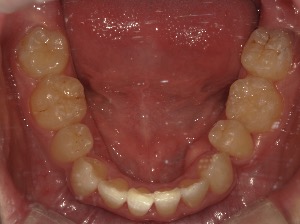

before

患者さんの年齢 30代 男性 症状 ガタガタを治したい 治療内容 ワイヤー矯正治療 費用 88万(税抜) 治療期間・回数 治療期間2年半、通院回数20回 メリット 口元が綺麗 デメリット・リスク 期間がかかることがある 患者さまの声 見た目が良くなった - 矯正治療